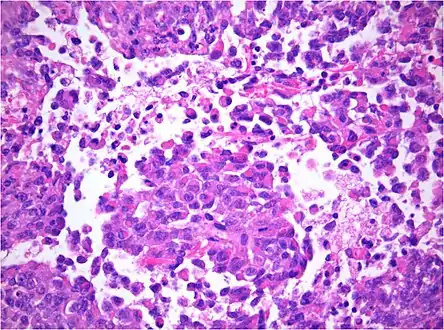

AT/RT and rhabdoid tumor share the term "rhabdoid" because under a microscope, both tumors resemble rhabdomyosarcoma.

AT/RT Histology with numerous rhabdoid tumor cells

Rhabdoid Tumor Cell - 400X Magnification

The tumor histopathology is jumbled small and large cells. The tissue of this tumor contains many different types of cells including the rhabdoid cells, large spindled cells, epithelial and mesenchymal cells, and areas resembling primitive neuroectodermal tumor (PNET). As much as 70% of the tumor may be made up of PNET-like cells. Ultrastructure characteristic whorls of intermediate filaments are seen in the rhabdoid tumors (as with rhabdoid tumors in any area of the body). Ho and associates found sickle-shaped embracing cells, previously unreported, in all of 11 cases of AT/RT.[16]